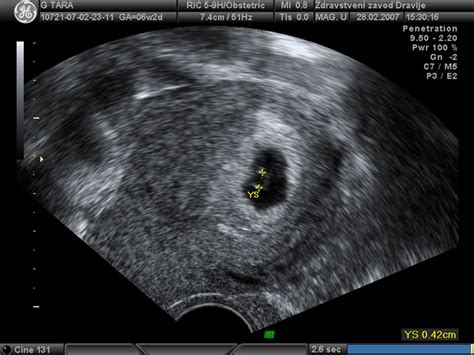

Če še niste imeli ultrazvoka v drugem trimesečju, je sedaj pravi čas zanj. Specialist bo preveril, kako plod raste, preveri lahko, ali so prisotne kakršne koli napake, ogleda si placento in popkovino, preveri, koliko plodov nosi nosečnica in ali je datum poroda točno določen. Tudi sami lahko med ultrazvočnim pregledom opazujete, kaj počne plod. Pregled za izključitev anomalij vam običajno ponudijo med 18. in 20. tednom. V preiskavi se podrobno pregleda otroka in ugotovi, ali je pri njegovem videzu in razvoju kaj nenavadnega. S pregledom je mogoče odkriti številne bolezni, vendar ne vseh. Večina pregledov pokaže zdrave otroke, če pa odkrije kaj nepričakovanega, vam bodo morda ponudili vrsto nadaljnjih testov.